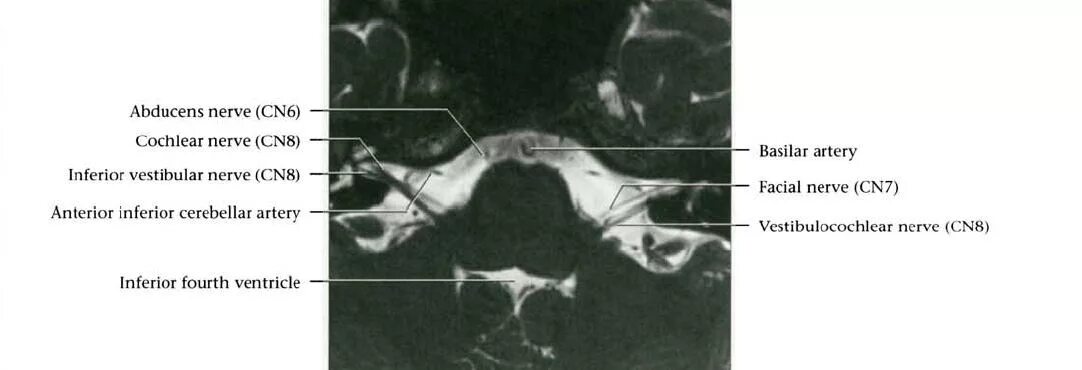

Нейроваскулярный конфликт нерва